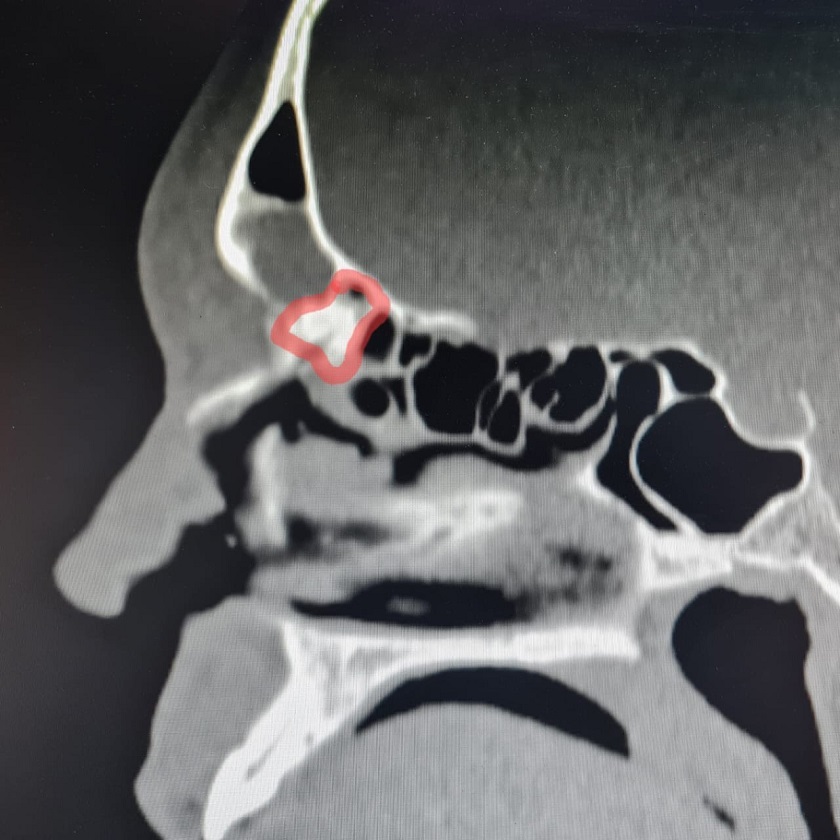

Елена Разумеева рассказала, что из-за вмешательства на лобной пазухе по поводу новообразования десять лет назад у пациента возникло нарушение дренажа слизи из лобной пазухи из-за перекрытия путей оттока вновь образованной костной и рубцовой тканью. Из-за скопления слизи начали разрушаться стенки пазухи, и калужанин испытывал сильную головную боль.

Фото: Елена Разумеева/Вконтакте. На снимке пазуха с блокированными путями оттока.